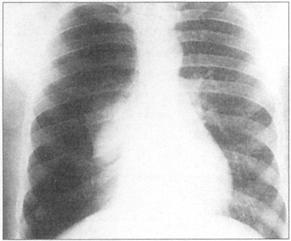

①周围性发绀及周围静脉扩张是由COPD引起的CO2潴留的主要特征(图76)。②脊柱侧后凸常预示患者有某种呼吸系统疾病的倾向(图77)。③结核的X线表现(图78)。④肺尖部结核所致的纤维化多引起上胸部变平(图79),由于脊柱常受累,故多有成角。⑤支气管肺癌(图80)。⑥大叶肺炎患者常伴发单纯疱疹病毒感染(图81、图82)。⑦如肺组织萎陷(如气胸),则胸片上无法看到肺纹理(图83)。

图78 结核,在肺上叶可见空洞

图79 肺尖结核。由于先前的结核靠造成拉平的顶端,伴有由脊柱弯曲引起的成角